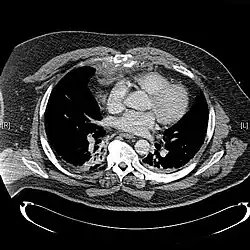

Diagnosis

X-rays of the chest are taken in people with chest trauma and symptoms of sternal fractures, and these may be followed by CT scanning.[13] Since X-rays taken from the front may miss the injury, they are taken from the side as well.[14]